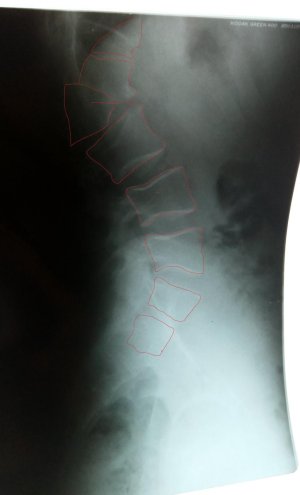

Диагноз: врожденный малый грудной кифоз, деформация позвонков в области пояснице.

Сделал ренген позвоночника с боковой проекцией - хирург - ортопед задавал много вопросов, наблюдался ли в детстве у специалистов - нет не наблюдался.

Хирург в местной поликлинике начал пугать что нужна срочная операция ( и вообще она должна была быть проведена в детстве) и как я вообще с таким позвоночником еще хожу.

Направили в в Минский РНПЦ травматологии и ортопедии. Записался на прием - таммографию не делал. Профессор посмотрел снимки, куда-то выходил в заключении написал: Оперативного лечения не назначено. Порекомендовал укреплять спинные мышцы спины спец упражнениями, воздержатся от тяжелых физических нагрузок.

Фото ренгена с обведенными позвонками плилагаю, и фото спины.